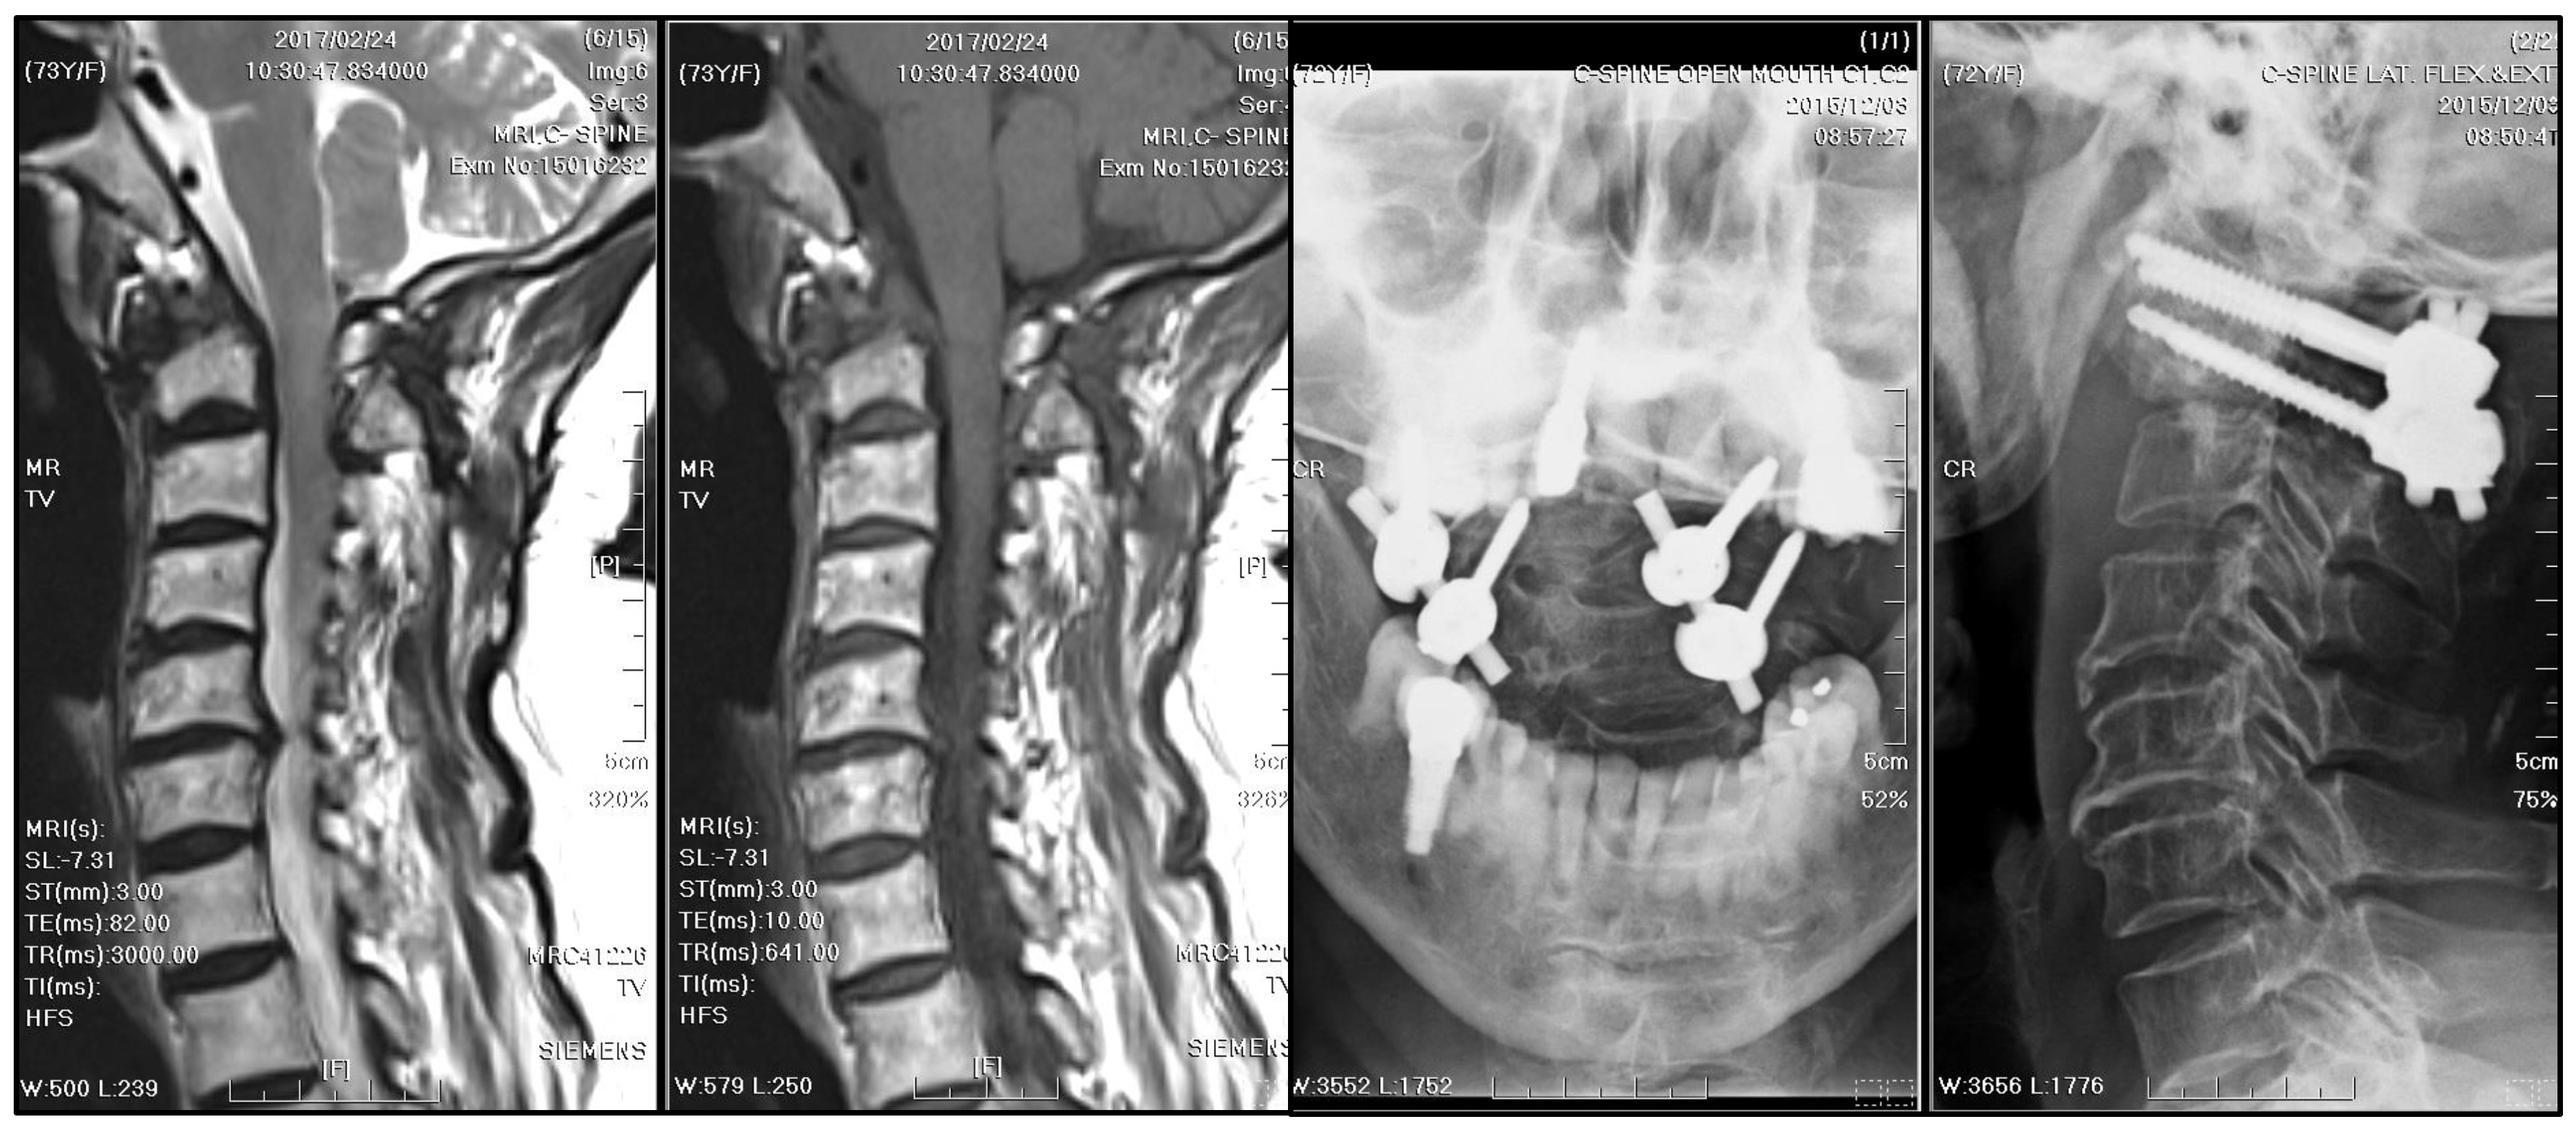

A radiographic examination of the cervical spine identified bony destruction of the C2 odontoid process and C1–C2 subluxation (Figure 1). Subsequent MRI with contrast enhancement and CT revealed an osteolytic lesion at C2, along with prevertebral and paravertebral soft tissue infiltration (Figure 2). The patient was suspected to have osteomyelitis, spinal tumor, or Langerhans cell histiocytosis. Prophylactic antibiotics cefazolin and metronidazole were administrated for one day prior to surgery.

Figure 3. Postoperative radiographs of the cervical spine: They were checked three weeks after a five-week course of antibiotics and posterior instrumented fusion with bilateral C1 lateral mass and C2 transpedicular screw fixation. The stabilization was fair.